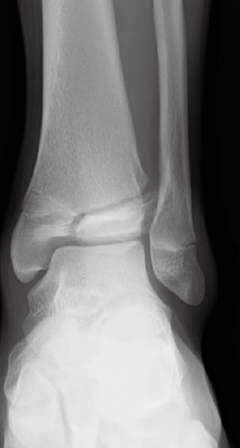

脛骨遠位骨端線損傷

脛骨遠位骨端線が閉鎖する時期に限定されます。Triplane 骨折は12~15 歳頃に好発する骨折で、脛骨の骨端線の閉鎖時期と閉鎖の仕方に関係しているとされています。

(図18) Triplane 骨折 左 レントゲン 右CT画像

(図18)MB Orthop. 38(5):55—64,2025大人とこどものスポーツ外来 下肢編【こども編】小児アスリートの足関節・足部捻挫に対する外来診療 田中 博史より抜粋

(図19)整形外科Surgical Technique vol.12 no.5 2022 52‐57(604‐609)[手術法] こどもの足関節周囲骨折・ Juvenile Tillaux・Triplane骨折 依光正則 より抜粋一部変更

Triplane 骨折は、Salter-Harris分類ではⅣ型にあてはまります。Ⅲ型は、Tillaux骨折といいます。脛骨遠位端骨折はⅠ/Ⅱ型が50%、Ⅲ型が25%、Ⅳ型が10%の頻度で発生するとされています。手術適応はⅡ~Vで考慮されます。Ⅴは骨端線がつぶれた状態です。